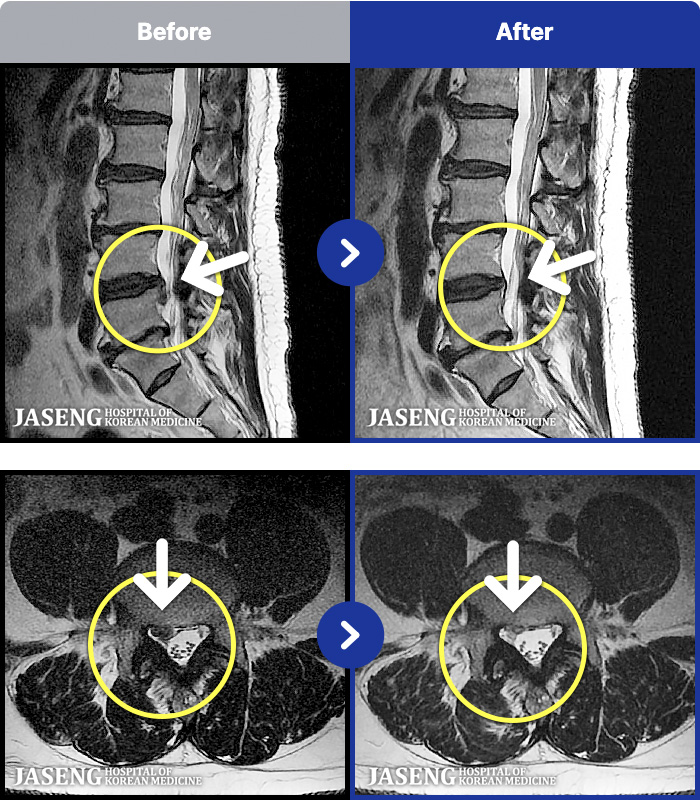

MRI ġ

54 MRI ũ ʸ Ȯϼ.

54

[Կñ:22.04.11~22.07.28]

[_㸮ũ] Ͽ ü Ÿ Ͽϴ.

No.54

ȸ 318

2026.01.09